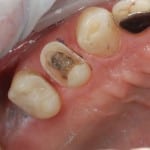

Ceramic Reconstruction step by step

This treatment provides a restoration made of ceramic material as similar to natural tooth (enamel) as anything yet devised. It is suitable for replacing old Crowns, Amalgam (mercury/silver) fillings and will last longer than current white fillings.